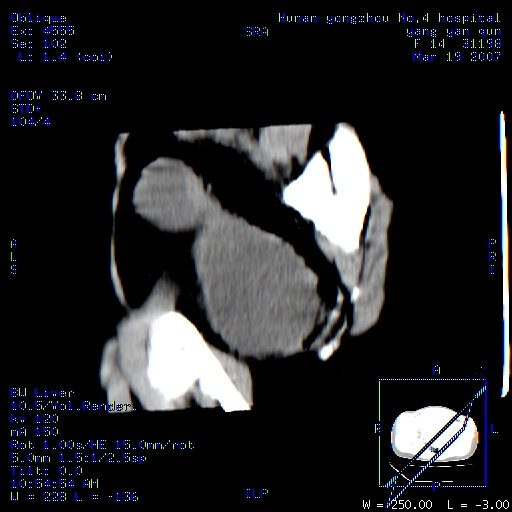

女,14岁,腹痛腹胀月余,患者发育正常,无月经史,检查发现下腹部肿块。患者碘过敏试验阳性。

子宫处见大的软组织肿块,考虑患者女性、14岁无月经,怀疑子宫发育异常

处女膜闭锁,阴道积血。

从矢状位上可见阴道部位明显增粗,内容密度较低,结合患者年龄和临床表现,首先考虑为先天性处女膜闭锁。

处女膜闭锁,阴道、子宫积血。

结合病史考虑处女膜闭锁致阴道、子宫积血。

处女膜闭锁致阴道、子宫积血。

考虑为先天性处女膜闭锁所致的阴道及子宫积血